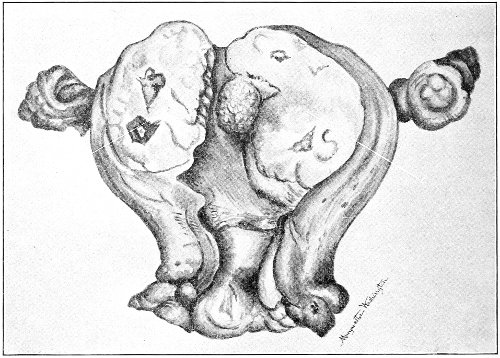

Cysts of the gland may be unilocular if formed at the expense of a single lobule of the gland, or multilocular if several lobules enter into their formation. These cysts may attain the size of the fetal head (Fig. 18).

Cysts of the gland or of the duct are formed by retention of the cyst-contents. The retention is due to occlusion of the duct, usually the result of inflammation. In some cases the duct remains pervious, and the retention is due to the altered character of the secretion of the gland, which becomes too viscous to pass, except under unusual pressure, along the duct.

These cysts contain clear yellow or chocolate-colored 42 fluid. The diagnosis of cyst of the vulvo-vaginal gland is usually not difficult. If we are in doubt in regard to the fluid character of the tumor, this may be determined with the exploring-needle.

Inguinal hernia, hydrocele of the canal of Nuck, cysts of the round ligament, and sacculated cysts of old hernial sacs may be mistaken for cysts of the vulvo-vaginal glands. In such cases, however, the tumor lies more in the upper and outer part of the labium majus, and extends to, and may be connected with, the external inguinal ring.

Cysts of the vulvo-vaginal glands should be treated by free incision and packing, or by extirpation. If the sac is emptied by the aspirator or by a small incision, it will refill. The best method is to extirpate the cyst. In case there has been no inflammatory action binding the cyst to surrounding structures, extirpation without rupture is easy. If rupture occurs, the cyst-wall may be dissected off with the knife or removed with the curved scissors. The wound may be immediately closed with deep and superficial sutures.